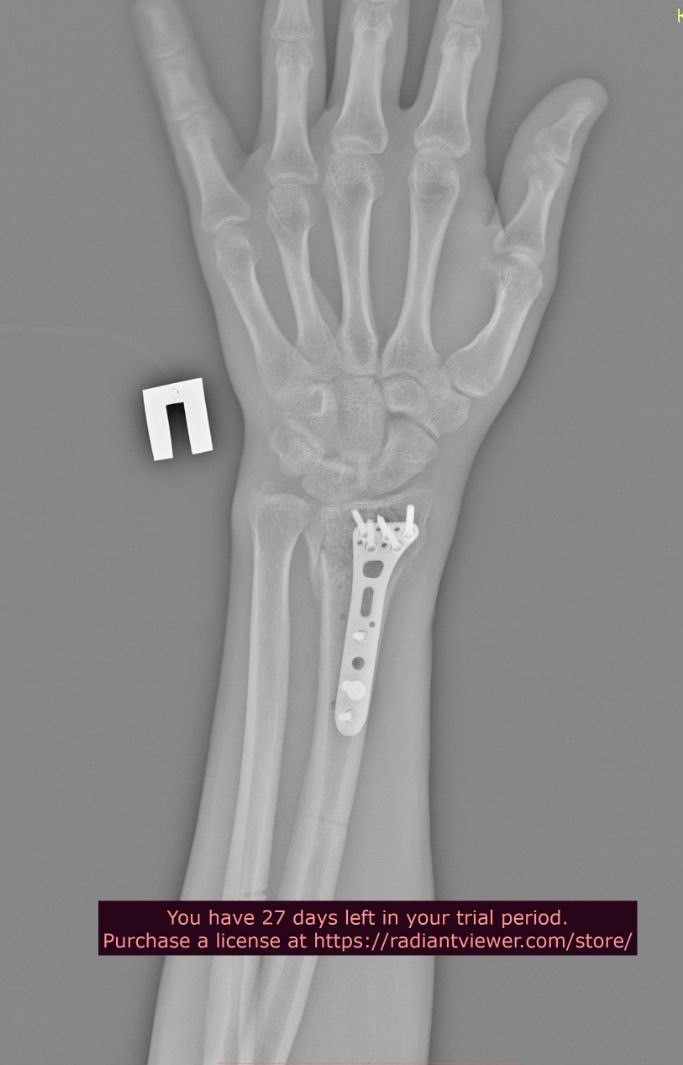

Добрый день. Два года назад упал с большой высоты, из-за чего мне установили металлоконструкции в плечевой и локтевой костях левой руки и в лучевой кости правой руки. Снимки ниже. Также имеются ограничения кисти на правой руке (из-за наличия пластины в лучевой кости), она разгибается максимум на 60 градусов из 90. Также, локтевая кость не разгибается до конца на пять градусов (что несущественно, но факт есть). Хотел бы уточнить, имею ли я возможность в моей ситуации получить категорию "В"? Спасибо.

Лучевая кость

Л11.jpg